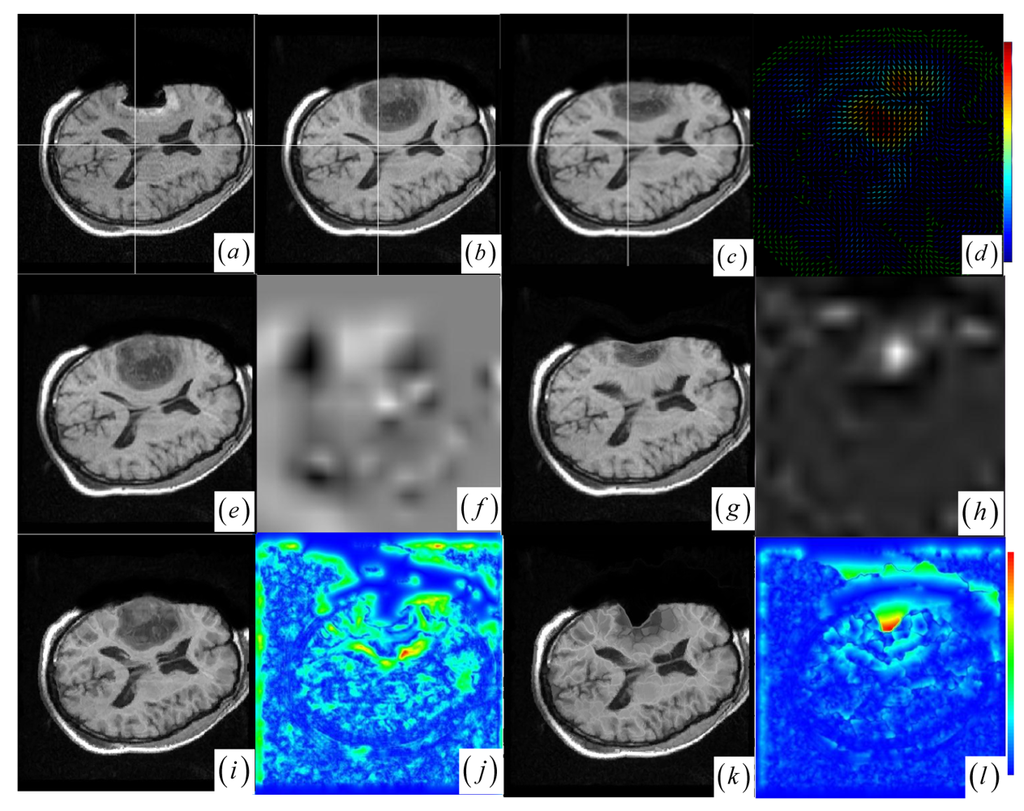

In contrast to four state-of-the-art intensity-based registration methods, including B-Spline with correlation ratio [56] (BCR), B-Spline with normalized MI (BMI) [34, 57], Demons (DEM) [58] and diffeomorphic Demons (DIF) [59], which are failed or unsatisfactory in tumor resection with outliers and local large deformation, our proposed method based on JSM & keypoint clustering (JKC) successfully model the tumor resection-induced brain shift (see Figures 34 and Table 1 cases 1–3). Table 1 summarizes the registration quality in terms of correlation ratio (CR) and normalized MI (NMI) [4, 60]. Figure 3a–d and Figure 4a–d show that the regions around the tumor areas have smoothly deformed to shift towards the tumor resection areas in the JKC registration results. The smoothly constructed deformation field is displayed by means of displacement vector field with variations of the vector color (from blue to red according to the displacement amplitude in pixels). The quality of these registration results also can be validated by the respective small CRs listed in the Table 1 cases 1–3. We also define the average error distance between the manually defined reference landmarks and the floating landmarks in the registered images (Figure 5 shows that most landmarks are around the tumor resection areas and the neighboring normal tissues), our method's average accuracy for the three cases of local large deformation (cases 1–3) achieves an average error distance of less than 1.2 pixel while the average accuracy for the two cases of small deformation achieves an average error distance of less than 1 pixel.

The BCR and BMI registration are implemented at two pass with the different transformation options (B-Spline degree for all axes: 1, 2; B-Spline control points for all axes: 8, 16; gradient descent minimize step size: 1.0, 0.5; gradient descent minimize maximum search steps: 10, 10) and the different iteration options (the convergence limit of minimum change rate for one iteration: 0.1, 0.01; maximum number of iterations: 10, 10) [57]. The dark areas on the deformation image (Figure 3f,h and Figure 4f,h) are related to the areas on the two images which did not perform a deformation during the registration or the deformation was relatively small. The light areas are related to the areas on the two images which perform a bigger deformation. In contrast to the BMI (Figure 3e,f and Figure 4e,f) that fails to compensate the local large deformation around the tumor areas, the BCR (Figure 3g and Figure 4g) can guide the anatomical structure deformation around the tumor resection regions (This also can be validated from the cases 1–3 at Table 1, at which the BCR have smaller CRs than the BMI, DEM and DIF). Nevertheless, the BCR has blurred and excessively shrunk the pre-operative anatomical structures around the tumor areas. From this experiment, we also confirm that the CR is more appropriate to be a similarity measure for the nonrigid monomodal registration of small structures than the NMI.

The DEM and DIF registration are conducted with a maximum step length of 2 pixels, 1.0 standard deviations of the Gaussian smoothing, a maximum number of 200 iterations and 0.001 intensity difference threshold. Treating each image as a set of iso-intensity contours and assuming the same anatomical point having the same intensity level in both images, the DEM and DIF easily distort the data to some extent, which may introduce strange artifacts similar to pieces of small mosaic patterns in the deformed pre-operative images (Figure 3i,k and Figure 4i,k). Additionally, the ”demons algorithm” with its large number of degrees-of-freedom allows to run into problems with the physical fidelity of the deformation field (Figure 4k and the DIF at case 2 in Table 1).

Figure 4. (a)–(b) Intra- and pre-operative MR images. (c) JKC. (d) Displacement vector field. (e) BMI. (f) BMI deformation image. (g) BCR. (h) BCR deformation image. (i) DEM. (j) DEM deformation image. (k) DIF. (l) DIF deformation image.